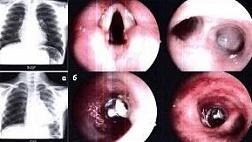

- Атлас